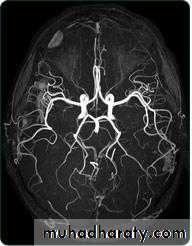

• Magnetic resonance angiography and magnetic resonance venography used for visualization of blood vessels with or without using contrast material.

• MRA is widely used in the imaging of the cerebral circulation and in some centers is the initial angiographic method of choice for other areas including the renal and peripheral circulations.